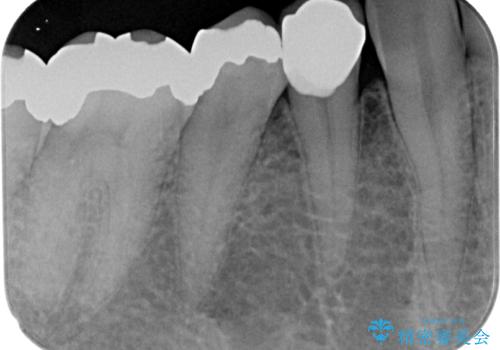

審美面、機能面共に満足していただけました。

順次、後ろにある不適合のメタルインレーの部位をやり替えていく予定です。